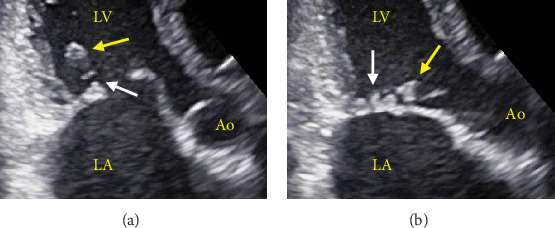

Papillary muscle rupture is a rare but serious complication during percutaneous transvenous mitral commissurotomy (PTMC). In many cases, it leads to acute significant mitral regurgitation (MR), requiring urgent surgical repair. We performed PTMC for a 49-year-old woman with symptomatic moderate rheumatic mitral stenosis. Initial balloon inflation resulted in papillary muscle rupture; however, it did not induce leaflet prolapse and worsening of MR. Finally, we succeeded in achieving a mean pressure gradient of less than 5 mmHg without worsening of MR through several balloon inflations. We experienced a rare case where papillary muscle rupture occurred during PTMC, but there was no development of acute significant MR, and salvage surgery was not required.